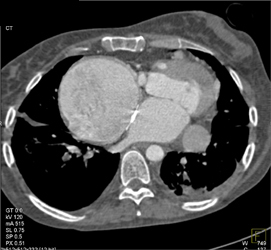

CASE NUMBER 623

Normal Coronary Arteries